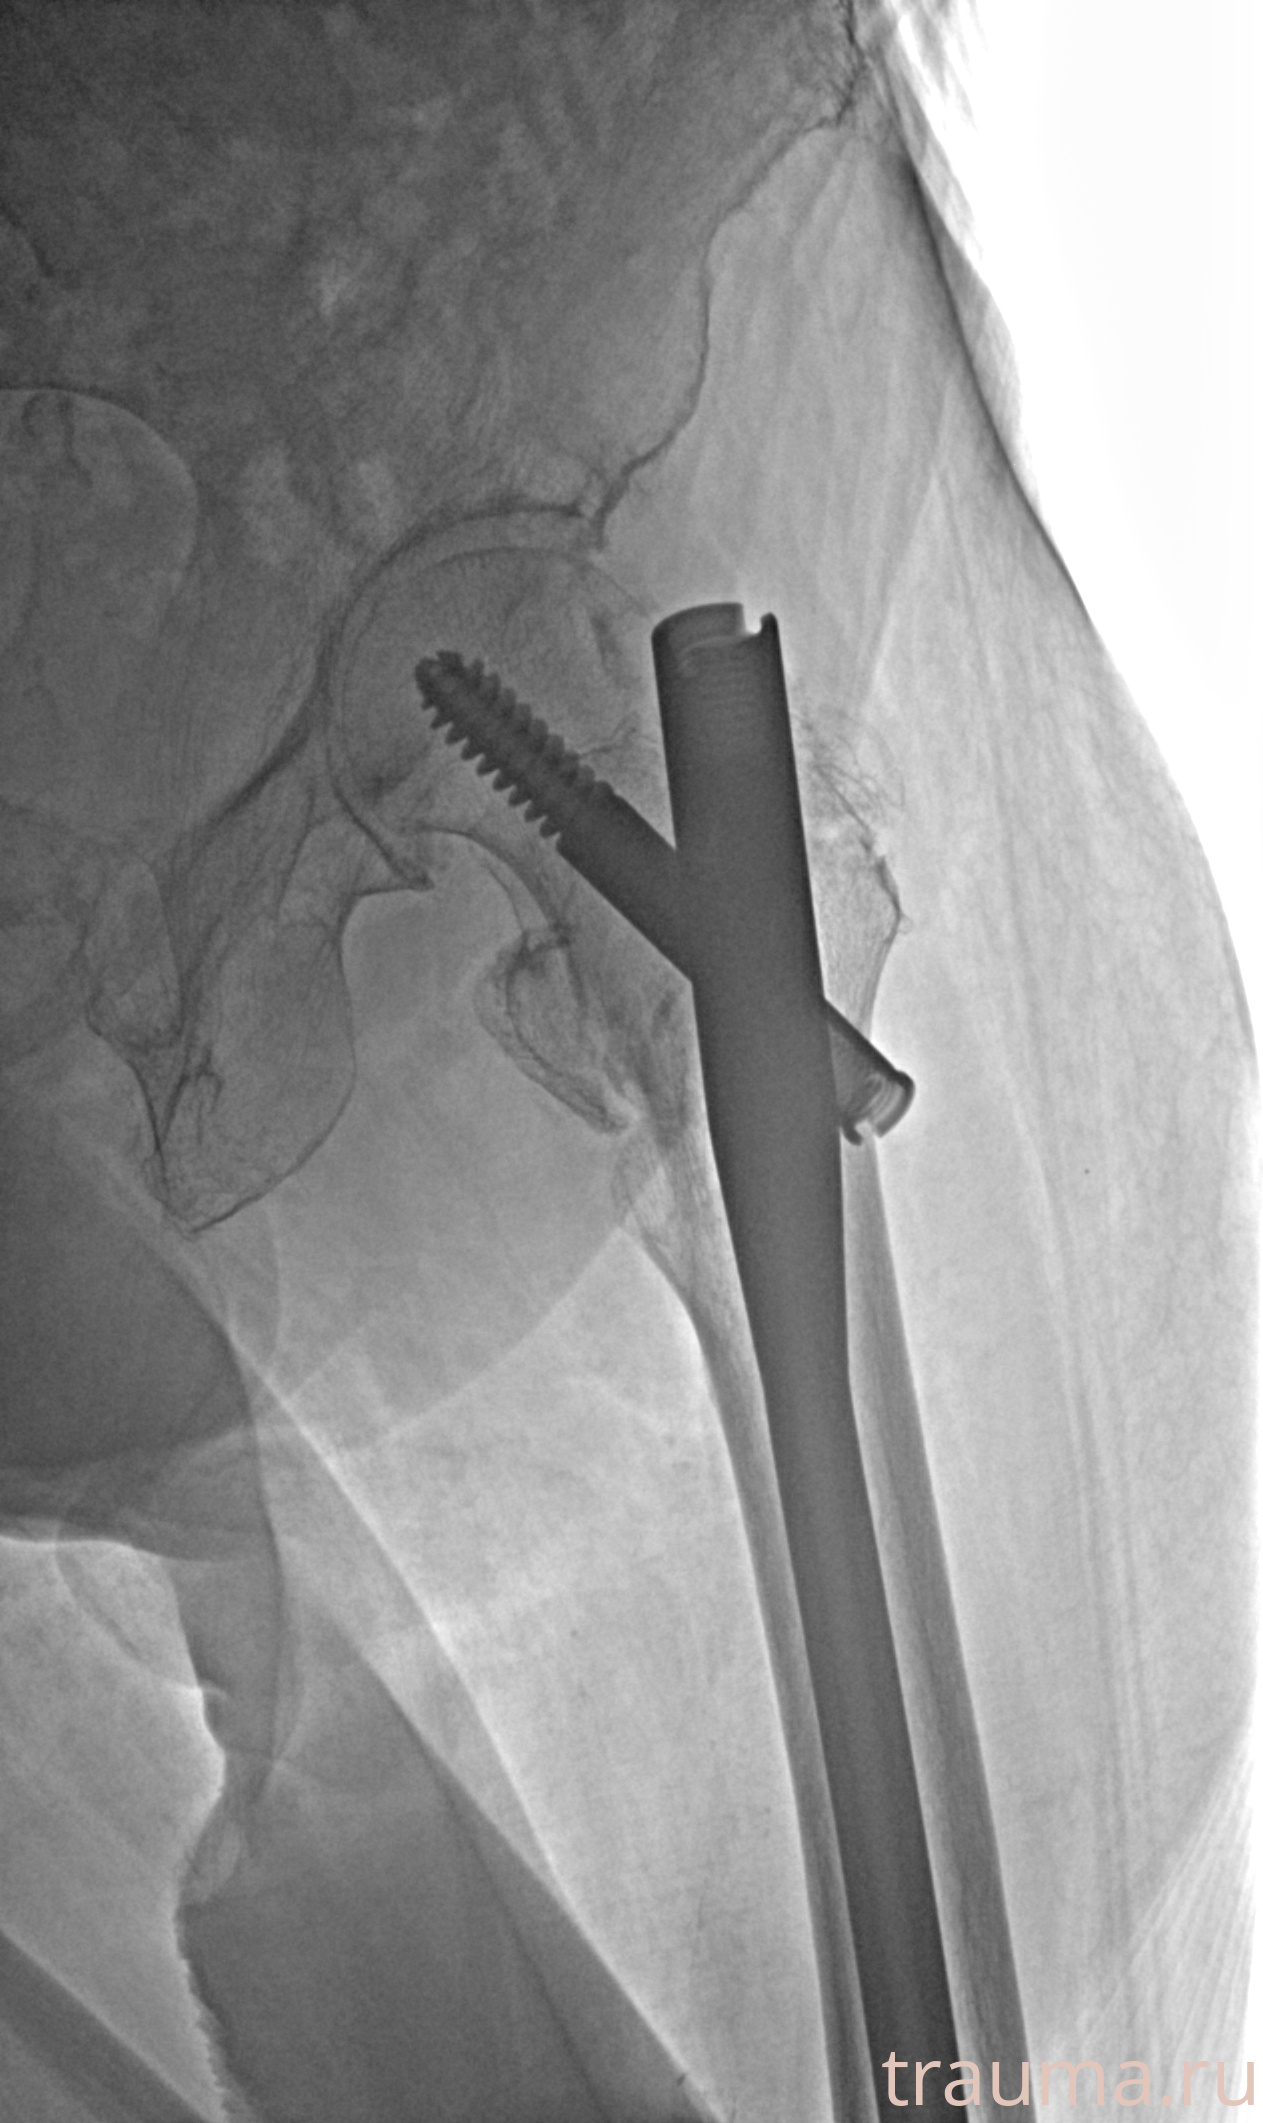

Рентгенограммы

Рентген на дому: по вашему адресу приезжает врач-рентгенолог, травматолог-ортопед с мобильным рентгеновским аппаратом, проводит диагностику травмы или заболевания, делает необходимые рентгенограммы, дает рекомендации по дальнейшему лечению. Получить качественные снимки в домашних условиях возможно благодаря уникальной методике, разработанной МосРентген Центром для института  Склифосовского